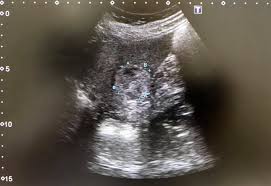

복부 초음파는 초음파(ultrasound)를 이용해 복부 내 장기들의 상태를 확인하는 비침습적 검사 방법입니다. 방사선을 사용하지 않아 인체에 해롭지 않고, 고통 없이 실시간으로 복부 장기들을 관찰할 수 있다는 점에서 가장 기본적이면서도 효과적인 진단도구로 평가받습니다.

초음파 탐촉자(Probe)에서 발생한 고주파 음파가 인체 내부 장기에 부딪혀 반사되며, 복부 초음파로 알 수 있는 것은 바로 이 반사파를 영상화해 간, 담낭, 췌장, 비장, 신장(콩팥), 방광, 대동맥, 림프절 등의 상태를 분석하게 됩니다.